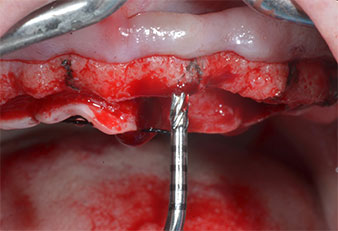

A flame-shaped, diamond-coated piezoelectric instrument (Piezomed I1) was used to mark the implant positions and to perform pilot preparation (Fig. 3). Care was taken to use an up and down movement, with reduced power, full irrigation and low pressure (below 300 g). Next a pilot instrument (Piezomed I2A/I2P) was applied for the initial 2 mm diameter enlargement of the implant sites (Fig. 4), followed by a 3 mm insert (Fig. 5).

In the present case the Z25P and Z35P instruments were not used due to the relatively soft posterior bone, which was easily managed with the I3A/I3P.